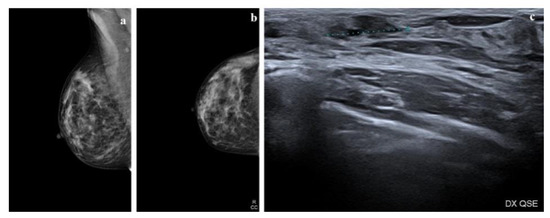

4. Radiologic Features